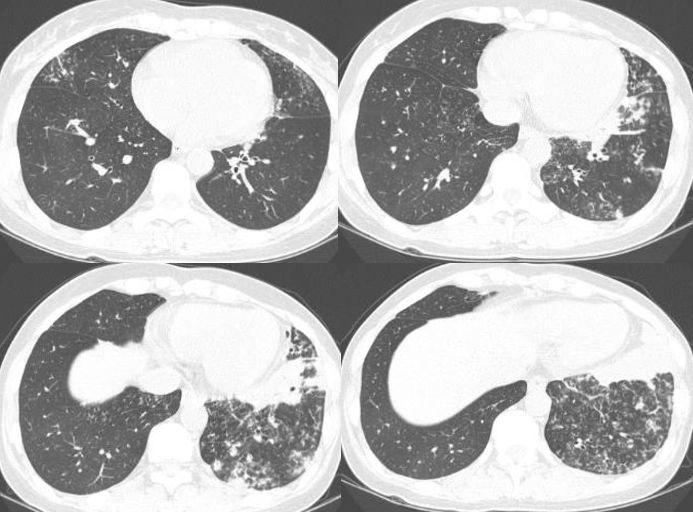

1、诊断:医生会根据患者的症状、体征、实验室检查和影像学检查等综合判断,确诊是否为肺炎。